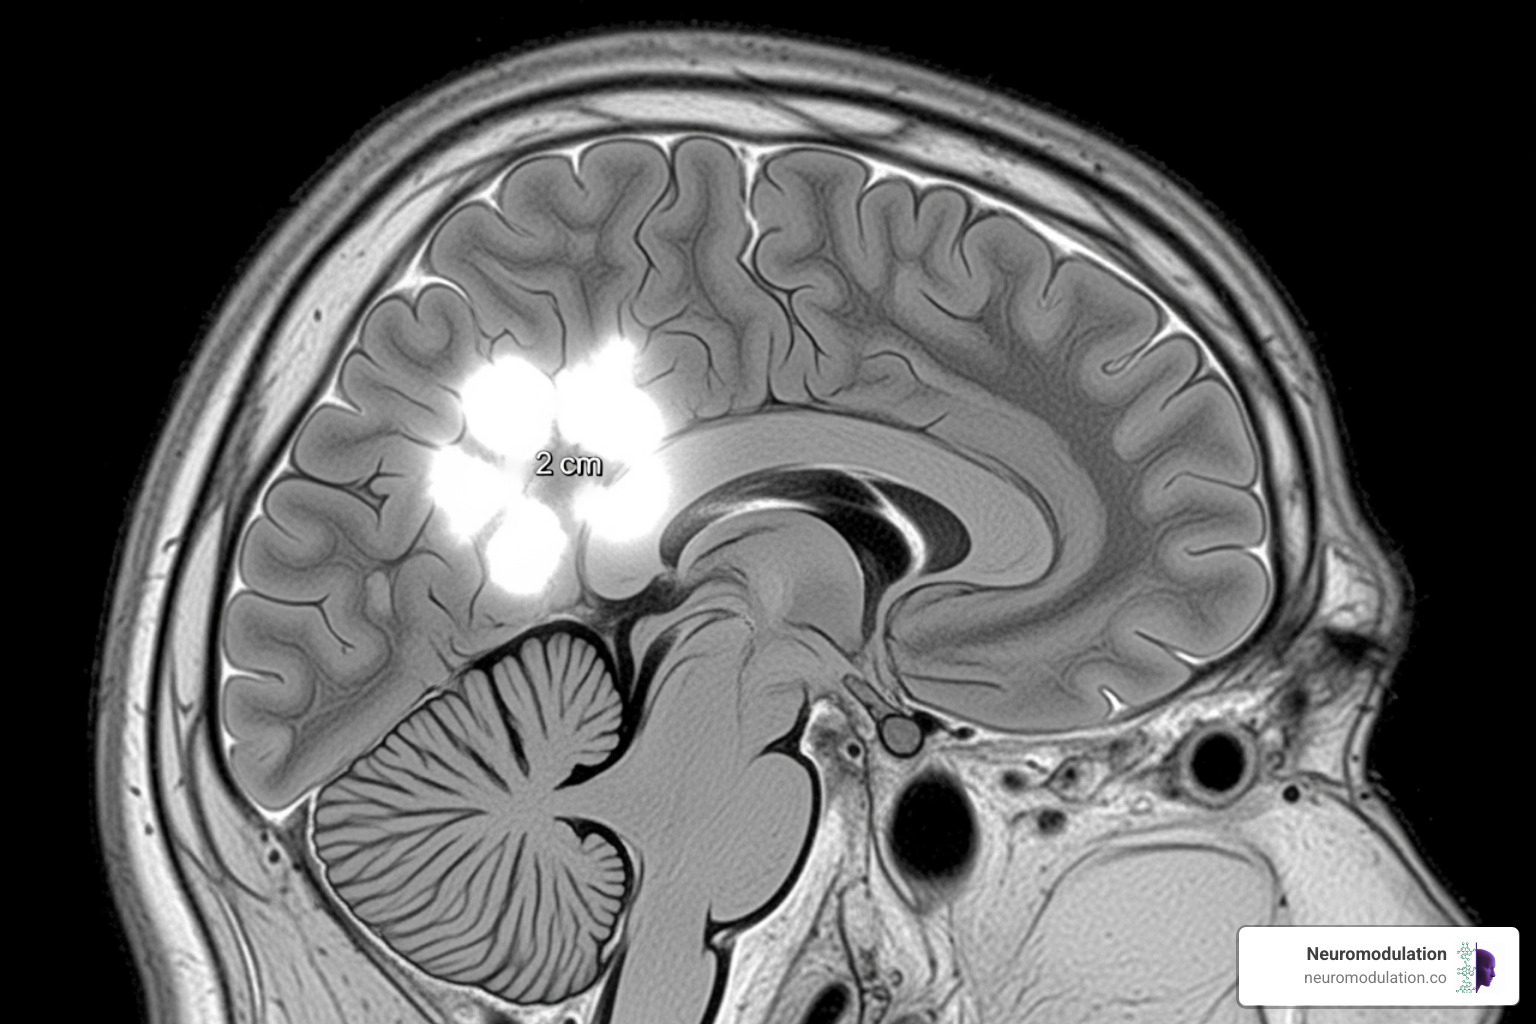

Superparamagnetic iron oxide nanoparticles (SPIONs) serve as powerful contrast agents in MRI scans. They improve images of brain tissue, helping surgeons delineate tumors or track inflammation in multiple sclerosis. They also show potential for early Alzheimer’s disease detection by highlighting amyloid-beta protein clumps.

This leads to the exciting field of “theranostics,” which combines therapeutics and diagnostics. A single nanoparticle can be engineered to both diagnose a disease and deliver treatment. For example, a brain specific drug delivery system could first highlight a tumor on a scan and then release its drug payload directly at the site.

This integrated approach is a major step toward personalized brain medicine, enabling real-time monitoring of treatment effectiveness. By targeting disease markers at their earliest stages, these tools offer the potential to diagnose and treat neurological conditions before they become severe.